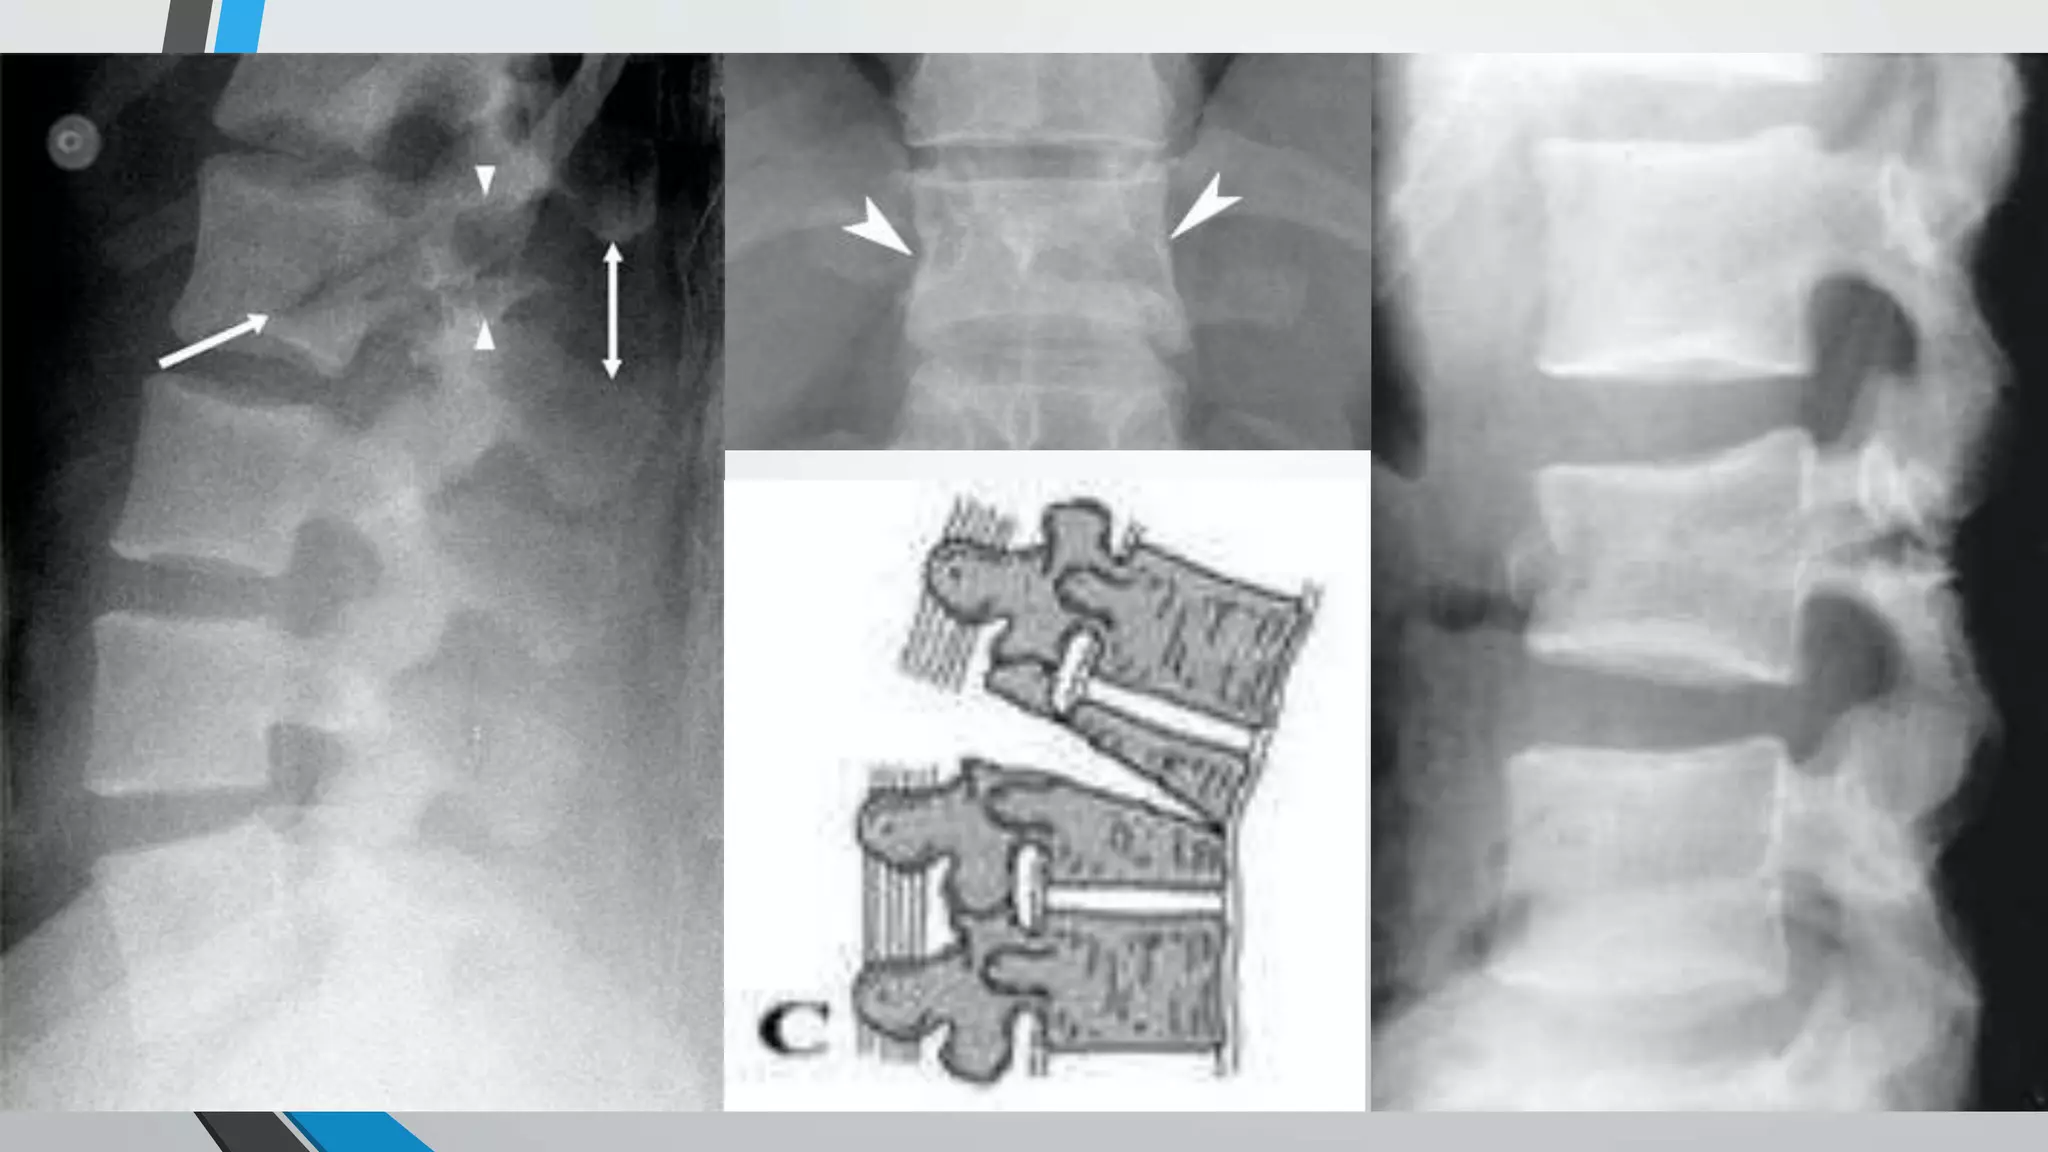

Denis Classification

• Fracture-dislocations

• All three columns have failed in compression, tension, rotation, shear

with translation deformity.

• At the affected level, one part of the spinal canal has been displaced in

the transverse plane